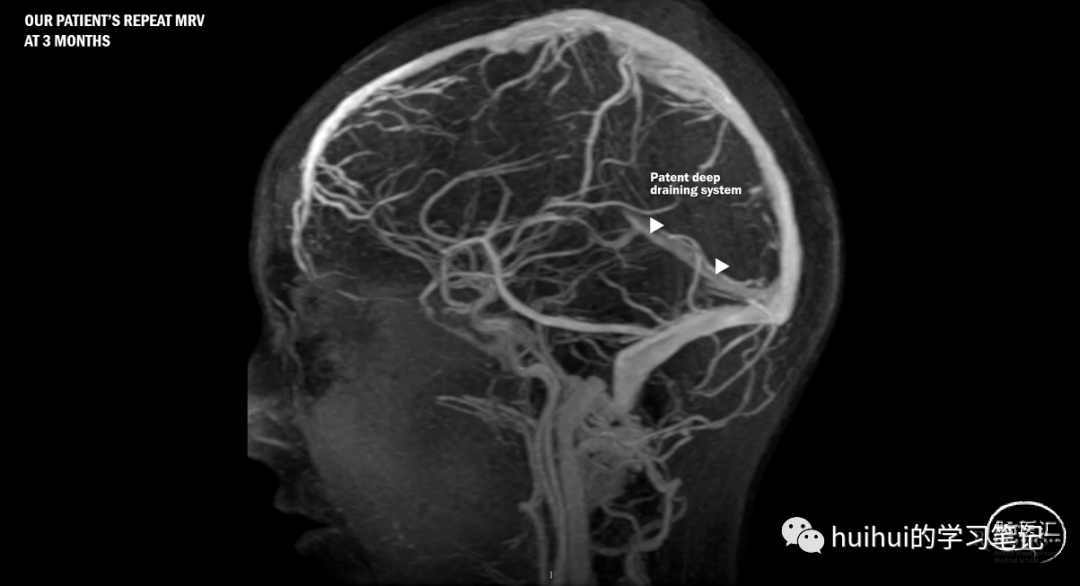

对于本例患者,血栓形成倾向检查结果为阴性,停用口服避孕药,并接受华法林治疗,滴定至 INR 目标为 2 至 3(该患者在 RE-SPECT CVT 试验发表前接受治疗),3 个月时重复成像……

复查影像:深层引流系统已完全重新通畅。这并不奇怪。 据报道,近 85% 的再通发生在治疗的前 3 个月。丘脑水肿消退,但梯度回波显示残余丘脑出血。